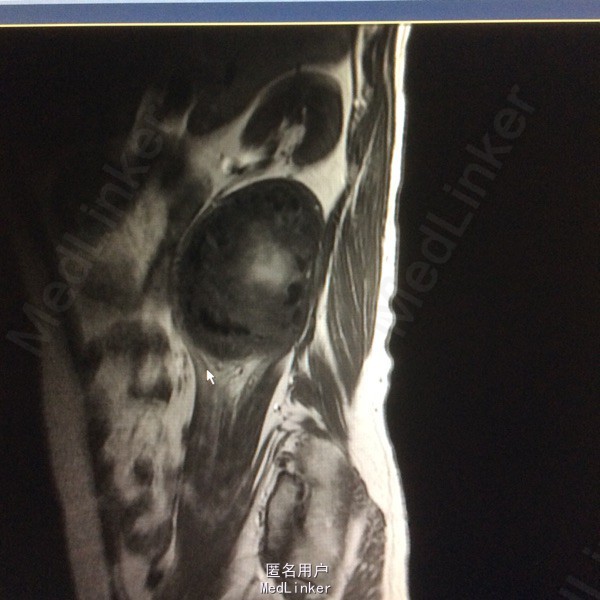

患者双下肢无明显浅感觉减退,肌力V级,肌张力不高,二便控制满意,病理征阴性。 腰椎核磁:腰1-4椎体右侧右肾下方团块状占位,大小约8#⃣6.8Cm,等T1长T2信号 腰椎Ct:占位周围见弧形钙化灶